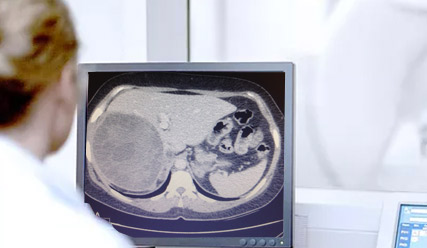

Quiste hidatídico

Son quistes benignos de comportamiento muy agresivo que se originan por la ingesta de deposiciones infectadas con huevos del parásito Echinococcus granulosus. Esta enfermedad en el humano se manifiesta principalmente en el hígado. El tratamiento salvo excepciones consiste en la extracción de todo el quiste el cual puede ser muy complejo según la ubicación que éste tenga dentro del hígado.